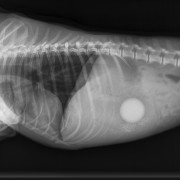

De testikel is verwijderd; het lieskanaal staat open

Het lieskanaal wordt dichtgehecht; dit is één van de belangrijkste handelingen

bij de castratie van het stinkdier